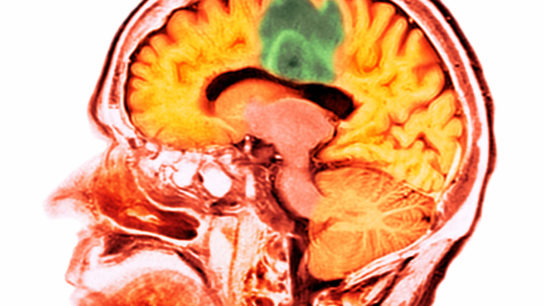

Researchers sought to develop and validate an MRI radiomics prediction model through a machine learning-based method to predict the survival of patients with glioma.